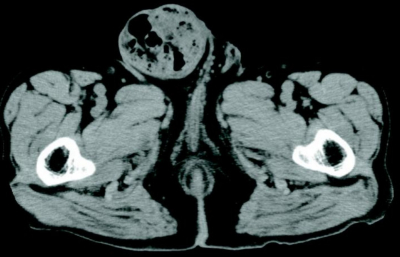

血液所見:赤血球459万、Hb 15.1g/dL、Ht 44%、白血球8,400、血小板25万。血液生化学所見:総蛋白7.7g/dL、アルブミン4.3g/dL、総ビリルビン0.9mg/dL、AST 26U/L、ALT 21U/L、LD 347U/L(基準120〜245)、CK 148U/L(基準30〜140)、尿素窒素18mg/dL、クレアチニン0.9mg/dL、血糖112mg/dL、Na 142mEq/L、K 4.2mEq/L、Cl 96mEq/L。CRP 0.9mg/dL。骨盤部CTを別に示す。

適切な対応はどれか。

a. 緊急手術